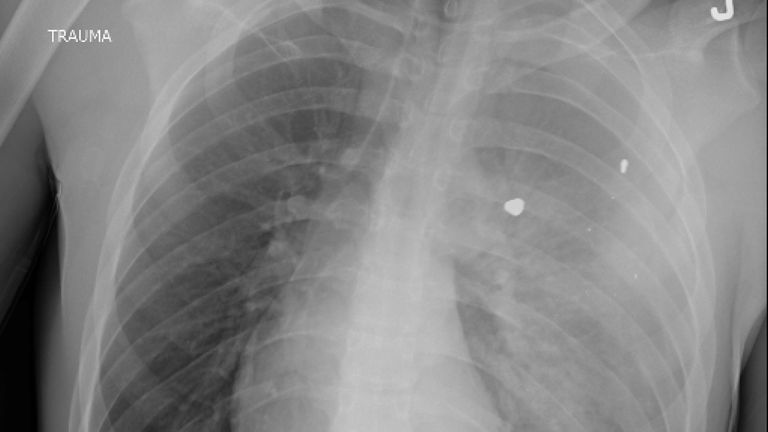

An emergency room doctor has shared a startling reminder that gunshots are the number one cause of death for children and teenagers in the US. Dr Sam Ghali shared the chest X-ray of "a young boy suffering from a condition that is now the #1 cause of death in children...